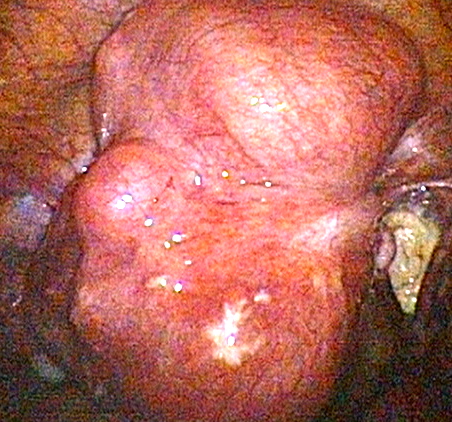

Examples of some pelvic masses dealt with by key-hole surgery.